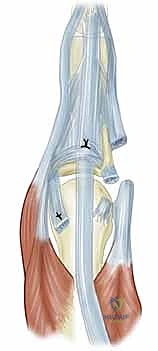

- وتر الباسطة الرقمية المشتركة (Extensor Digitorum Communis - EDC): هو اللاعب المركزي والنجم في إجراء اليوم الجراحي. يتم الاحتفاظ بهذا الوتر في المنتصف تماماً فوق قمة مفصل MCP بواسطة هياكل تُعرف بـ الأربطة السهمية (Sagittal Bands).

- الأربطة السهمية: هي ألياف مستعرضة قوية تنشأ من غطاء الباسطة (Extensor Hood) وتتصل من الناحية الراحية بالصفيحة الراحية والرباط بين الأمشاط المستعرض، لتشكل آلية تشبه "الحبال" أو "المقلاع" (Sling mechanism) تحافظ على الوتر في مكانه. يُعتبر الرباط السهمي الزندي عموماً أقوى وأكثر كثافة من نظيره الكعبري، وهو عامل بيوميكانيكي يساهم في سهولة انزلاق الوتر نحو الجهة الزندية (Ulnar Subluxation) عندما يضعف الرباط الكعبري بسبب المرض.

- تمزق الرباط السهمي الكعبري (Radial Sagittal Band Attenuation): التورم المستمر يضغط على الأربطة السهمية التي تثبت الوتر الباسط. نظراً لأن الرباط الكعبري أضعف بطبيعته، فإنه يتمدد أو يتمزق أولاً.

- الانزلاق الزندي للوتر الباسط (Ulnar Subluxation of EDC): بمجرد ضعف الرباط السهمي الكعبري، ينزلق وتر الباسطة (EDC) من أعلى قمة المفصل نحو الوادي الزندي بين الأمشاط. عندما يحدث هذا، يفقد الوتر قدرته على بسط الإصبع بفعالية، وبدلاً من ذلك، تصبح قوة سحبه مساهمة في زيادة الانحراف الزندي للأصابع.